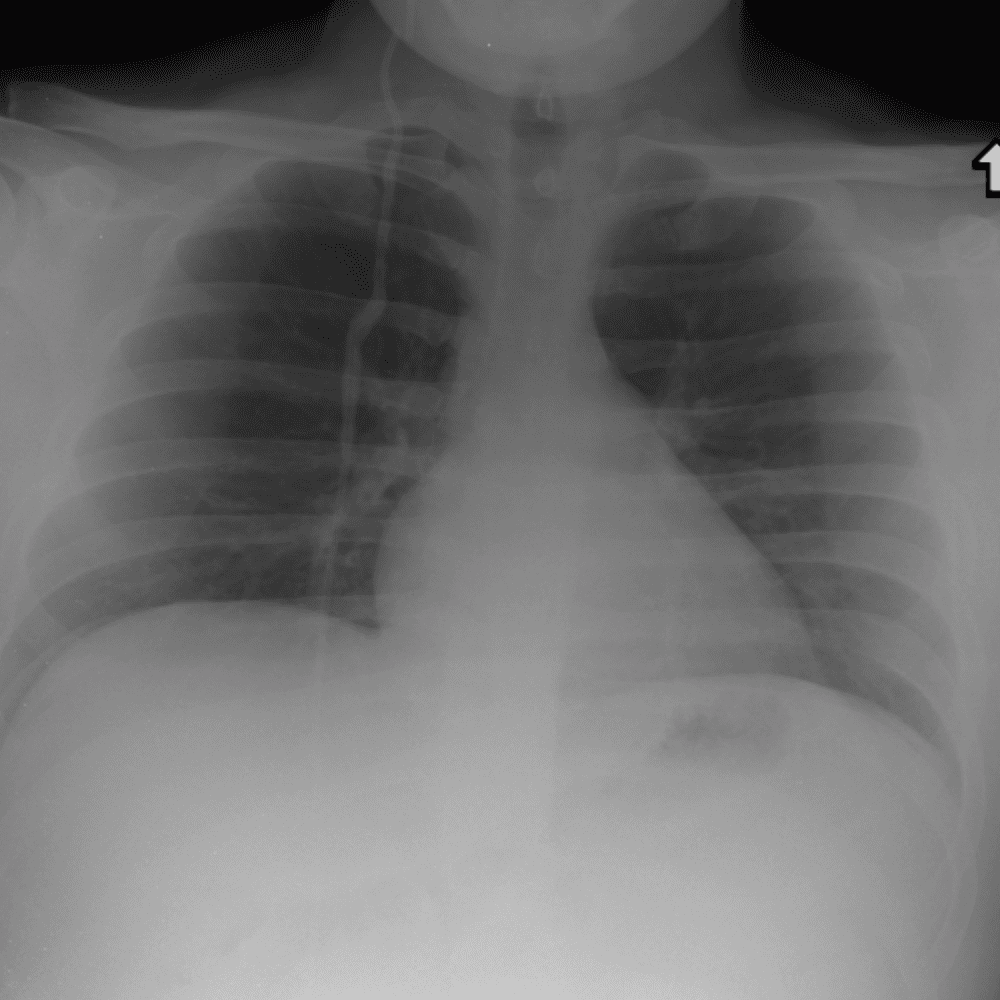

Practice Cases